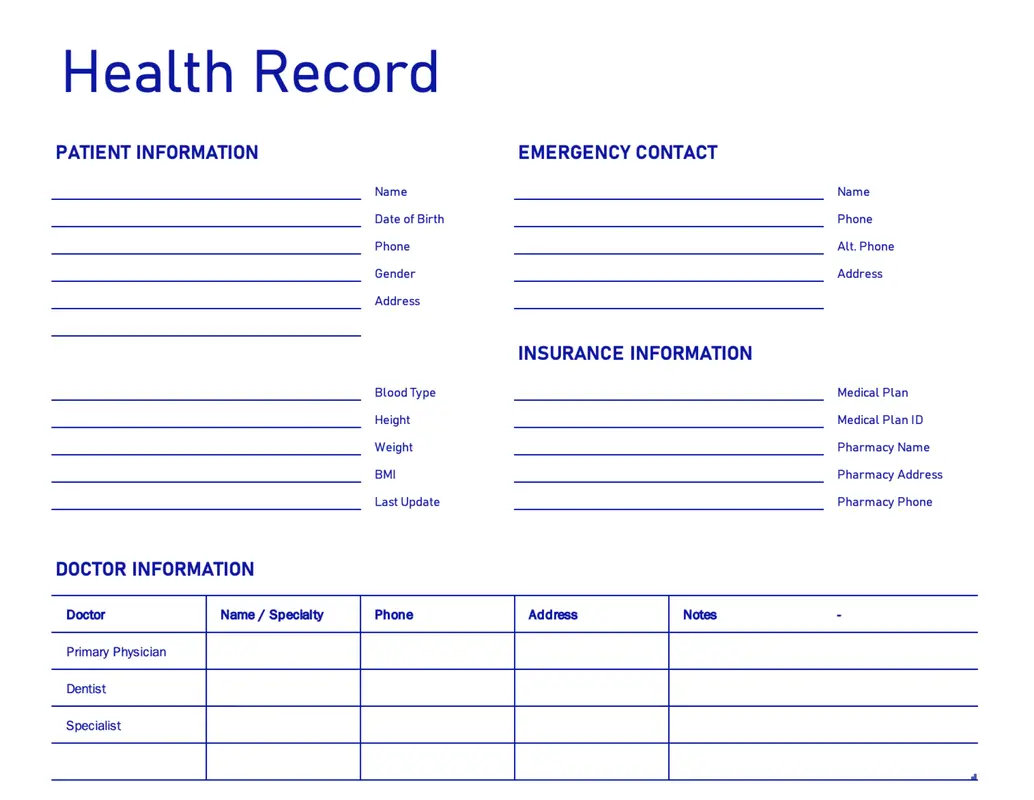

PowerPoint, Excel, Designer, Word를 사용하여 전문적인 의료 서비스 템플릿을 쉽게 맞춤 편집하세요. 각 템플릿은 완벽하게 맞춤 편집 가능하며 텍스트, 이미지, 글꼴을 변경하거나 동영상 또는 애니메이션을 추가할 수도 있습니다. 템플릿은 어디에나 공유하고 게시할 수 있습니다. 환자에게 병이나 질환에 대해 설명하는 데 도움이 되는 프레젠테이션 템플릿을 찾아보세요. 또한 의료 서비스 분야 비즈니스에 대한 피치 덱으로 사용할 수 있는 프레젠테이션 템플릿도 있습니다. 의료 서비스 종사자가 아니더라도 가족의 건강 정보와 의료 기록을 정리하는 데 사용할 수 있는 무료 건강 기록 템플릿을 활용할 수 있습니다. 또는 운동 계획, 기분 기록지 또는 칼로리 기록지와 같은 템플릿을 찾아보고 건강 상태를 빠르게 파악하세요. 의료 행위 또는 의료 기관 관련 소셜 미디어를 운영하는 경우 수십 개의 소셜 미디어 템플릿을 확인할 수 있습니다. 세계 에이즈의 날, 유방암 인식 제고의 달 등 다양한 건강 행사를 위해 만들어진 템플릿을 사용하여 인식을 확산하세요. 이러한 각 템플릿은 Facebook, Instagram 또는 Twitter에 적합한 형식으로 제작할 수 있습니다.